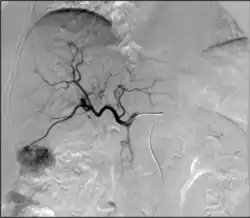

ангиография артериита Такаясу

Расслоения могут возникнуть практически в любой другой артерии. Например, расслоение сонной артерии повышает риск инсульта у пациентов и может распространиться дальше на кровеносные сосуды головного мозга. Расслоение позвоночной артерии встречается реже, но также опасно по тем же причинам. Расслоение брыжеечной артерии может ограничить кровоснабжение кишечника. Расслоение почечной артерии может привести к снижению притока крови к почкам и способствовать гипертонии.[39] Расслоения периферических артерий могут наблюдаться и в других местах рук и ног. Эти расслоения могут возникать в основном из-за очаговых травм, сопутствующих сосудистых заболеваний или как продолжение более крупного, сложного расслоения аорты, которое далее проникает в эти более мелкие ветви.